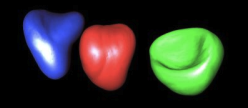

Statistical Shape Models Based on Correspondence Probabilities and the EM-ICP Algorithm

The goal of this project is the development of model-based methods for automatic 3D segmentation and recognition of anatomical structures in medical images. A statistical shape model is generated using point cloud representation of the instances. In order to avoid typical problems of direct point-to-point correspondences, a correspondence probability approach is realized when registering the instances (see figures 1 and 2).

Contacts: Xavier Pennec